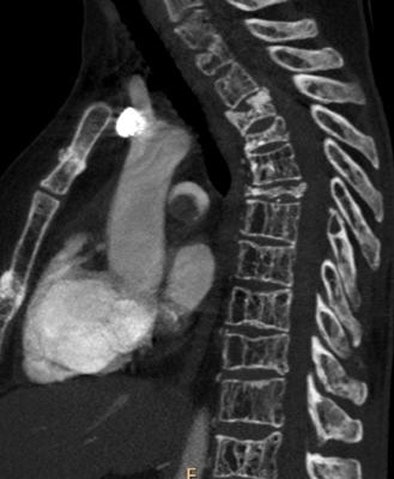

| Sagittal image shows a massive filling defect in the pulmonary trunk. Multiple vertebral and sternal fractures are also depicted. |

The results showed PE in 73 (30.5%) of 239 patients; of these cases, 45 (61.6%) were categorized as massive and 28 (38.4%) as nonmassive.